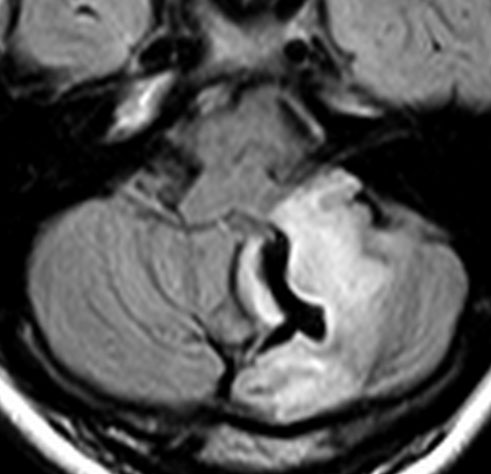

思春期の女の子にできた小脳腫瘍です。とても大きく見えますがほとんどが水たまり(のう胞といいます)。第4脳室が腫瘍で圧迫されて閉塞性水頭症になりました。のう胞の中に出血がありますが毛様細胞性星細胞腫では腫瘍内出血をしばしば見ます。右の写真で脳室が大きくなっています。こんなに大きいのに小脳症状は全くなくて,頭痛と嘔吐が症状でした。

赤で塗ったところだけが毛様細胞性星細胞腫です。これを取れば治ります。簡単な手術ですし後遺症も残りません。

手術後のMRIです。水頭症も改善してますから症状も消失しましたし,すぐに退院です o(^o^)o